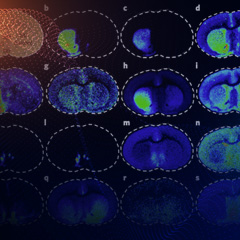

本设备适用于原位分析固体样品(如组织切片),并进行高灵敏分子成像。其原理基于解吸附电喷雾离子化,因此无需喷涂基质,可以广泛适用于各类小分子,如代谢物、药物、多肽、脂类等精确分子成像。通过精确控制喷雾电流的启动和暂停,有效地使分析物离子产生与质谱的离子注射时间同步,最大化离子利用率,从而提高灵敏度,扩展可覆盖的分析物数量。